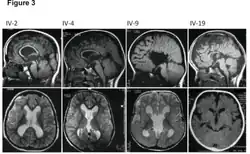

| MRI images showing megalencephaly in four family members who all have unusually large skulls (the family is affected by an autosomal recessive syndrome caused by a KIF7 mutation that induces multiple epiphyseal dysplasia)[1] | |

A neurological exam will then be performed using the technology of an MRI machine in order to confirm the diagnosis of megalencephaly. These imaging tests give detailed information regarding brain size, volume asymmetry and other irregular developments linked with MCAP, MPPH and hemimegalencephaly.[2][21]